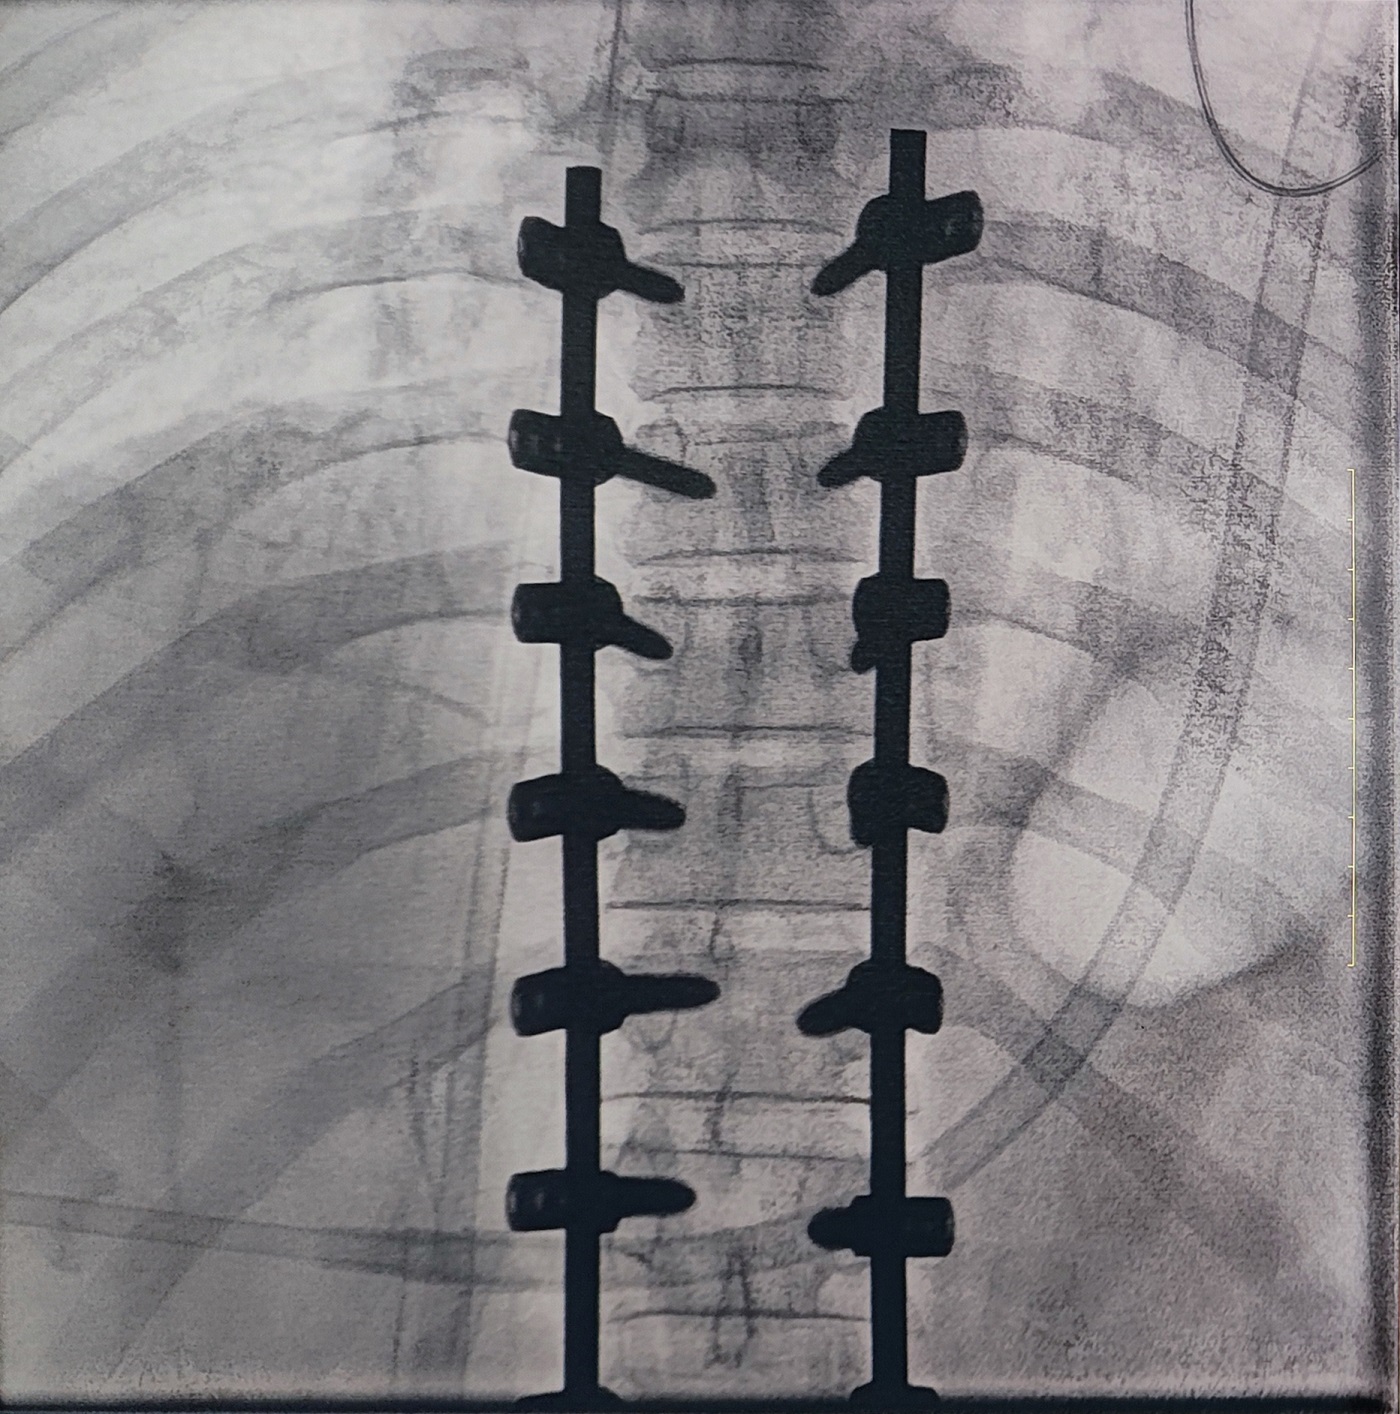

一場(chǎng)脊柱手術(shù)中,醫(yī)生需要拍攝跨越7個(gè)節(jié)段的脊柱影像,由于曝光的視野較大,常規(guī)視野的C形臂通常需要拍攝2-3次,普愛醫(yī)療大平板一體式C形臂30CM*30CM的“大視野”,輔助醫(yī)生一次性完成了7個(gè)節(jié)段的拍攝。最終,醫(yī)生在高清影像的輔助下完成了14枚螺釘?shù)木珳?zhǔn)定位、置入。

大視野,不僅意味著醫(yī)生可以更快,獲取更全面的影像信息,做出精準(zhǔn)判斷,無需多次拍攝定位,也顯著地降低了患者接受的輻射劑量。